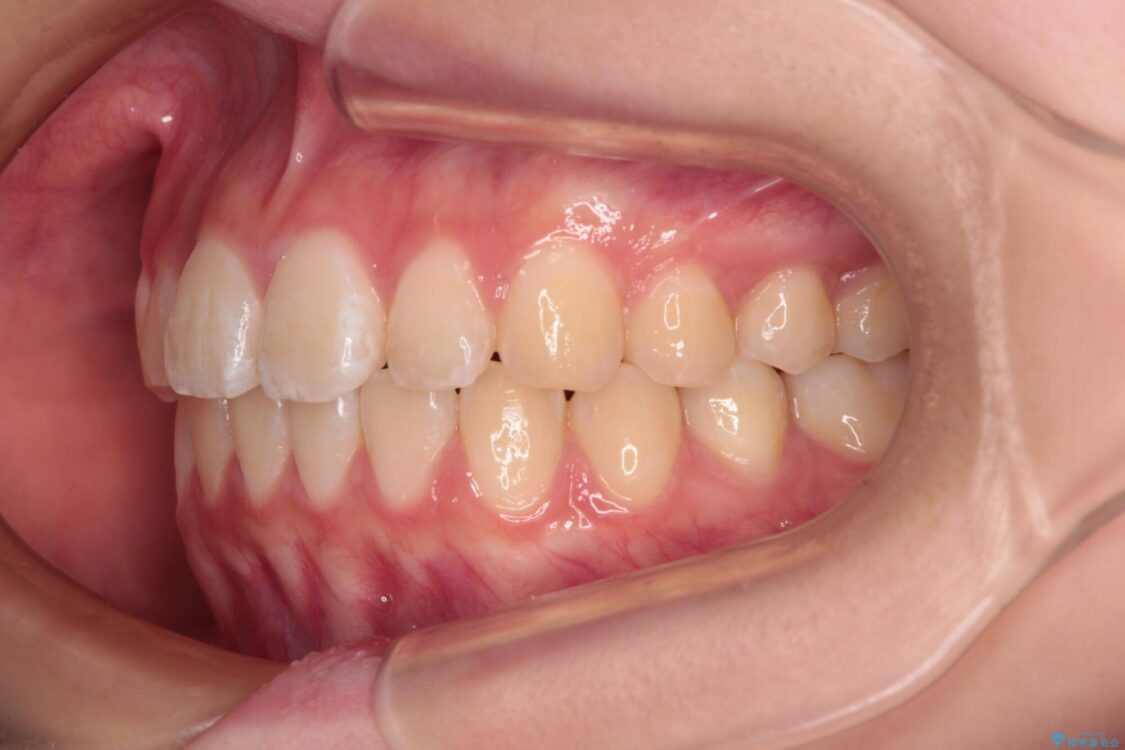

治療後

• インビザラインは使える自信がない ワイヤー装置にて矯正治療 治療後画像